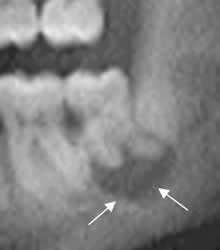

Fig 56. Quiste radicular.

Ortopantografía. Imagen radiolúcida, que rodea las raíces de la pieza dental y compatible con quiste radicular.